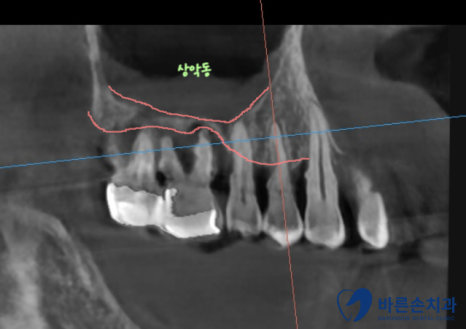

임플란트를 하기 전 CT 사진을 촬영하고 더 자세한 뼈 상태를 봤습니다.

임플란트를 심기 위해서는 최소 8~10mm 정도의 뼈가 있어야 하는데

치주병으로 인해 뼈가 종잇장처럼 얇게 있습니다.

뼈 위에 있는 비어있는 공간 상악동을 활용해서

뼈이식을 하고 임플란트 식립하기로 합니다.